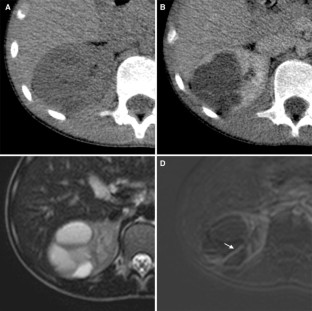

Fig. 1